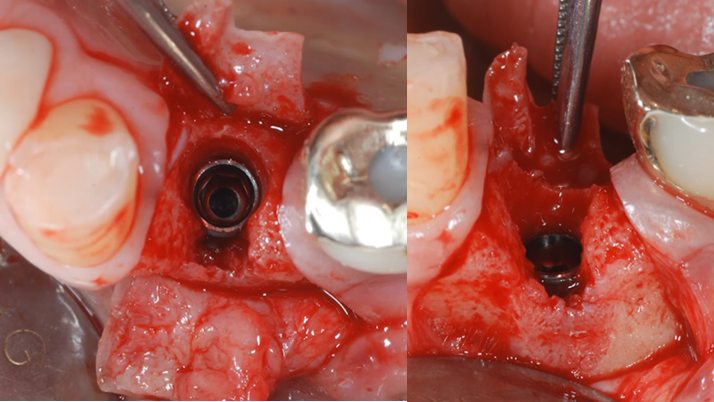

Clinical case: EImmediate implant placement & loading of #35 extraction socket with defect

- Courtesy of Dr. Kwang Bum Park, Korea -

Keywords

Dr. Kwang Bum Park, immediate loading, digital guided surgery, digital ONE-DAY implant, maxillary anterior, #21, guided surgery, immediate loading, AnyRidge, R2GATE, Mega ISQ, MEG Torq, R2GATE Full Surgical Kit

Products:

implant system, R2GATE Guide, R2GATE surgical kit (AnyRidge), Mega ISQ, Mega-Oss

“ One implant /One tooth/ One hour step-by-step

+ associated connective graft ”